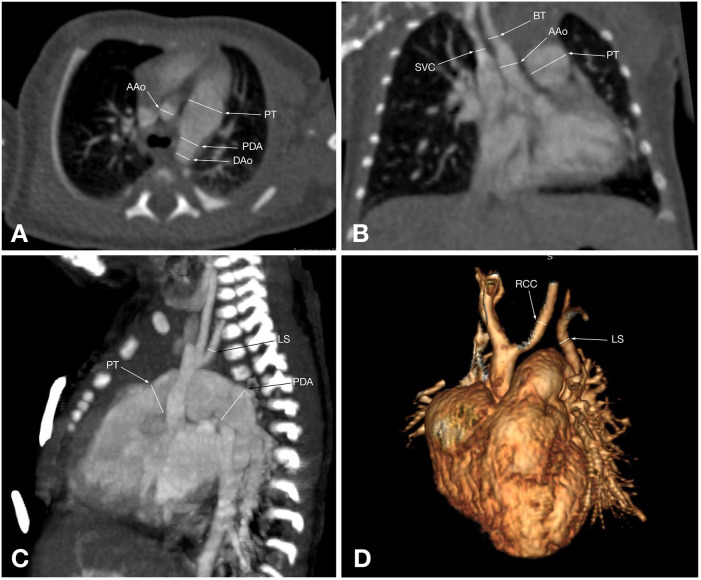

主动脉弓中断(IAA)是一种罕见的先天性心血管异常,其特征是升降主动脉之间缺乏连续性,通常伴有先天性心脏缺陷,如室间隔缺损和动脉导管未闭。准确的术前影像对手术计划和患者管理至关重要。本研究旨在比较超声心动图和计算机断层血管造影(CTA)在评估IAA患者胸部表现方面的诊断准确性。对2020年9月至2023年1月期间在哈萨克斯坦阿斯塔纳大学医学中心心脏中心诊断为IAA的58例患者(中位年龄:18天)进行了回顾性分析。常规超声心动图和多层CTA采用标准化方案。计算敏感性、特异性和其他诊断性能指标。采用McNemar和Wilcoxon有符号秩检验进行统计学比较,p p p = 0.09)。IAA主要为A型(48.3%)和B型(46.6%),34.5%的患者发现升主动脉发育不全。超声心动图仍然是IAA的一种实用的初始成像方式,具有便携性和成本效益。然而,CTA显示出优越的诊断准确性和解剖分辨率,使其成为详细的术前评估和手术计划的首选工具。未来有更大的队列和其他方式的研究可以进一步完善IAA的诊断策略。

Interrupted aortic arch (IAA) is a rare congenital cardiovascular anomaly characterized by the absence of continuity between the ascending and descending aorta, often accompanied by congenital heart defects such as ventricular septal defects and patent ductus arteriosus. Accurate preoperative imaging is essential for surgical planning and patient management. This study aimed to compare the diagnostic accuracy of echocardiography and computed tomography angiography (CTA) in evaluating thoracic findings in patients with IAA. A retrospective analysis was conducted on 58 patients (median age: 18 days) diagnosed with IAA between September 2020 and January 2023 at the Heart Center, University Medical Center, Astana, Kazakhstan. Conventional echocardiography and multislice CTA were performed using standardized protocols. Sensitivity, specificity, and other diagnostic performance metrics were calculated. Statistical comparisons were made using McNemar's and Wilcoxon signed-rank tests, with p < 0.05 considered significant. Echocardiography correctly identified 91.4% of IAA cases, while CTA achieved 100% sensitivity and specificity. McNemar's test revealed a significant difference in diagnostic performance favoring CTA (p < 0.05). Measurements of the ascending aorta diameter showed no statistically significant difference between the two modalities (p = 0.09). IAA was predominantly type A (48.3%) and type B (46.6%), with hypoplastic ascending aorta identified in 34.5% of patients. Echocardiography remains a practical initial imaging modality for IAA, offering portability and cost-effectiveness. However, CTA demonstrated superior diagnostic accuracy and anatomical resolution, making it the preferred tool for detailed preoperative evaluation and surgical planning. Future studies with larger cohorts and additional modalities could further refine diagnostic strategies for IAA.